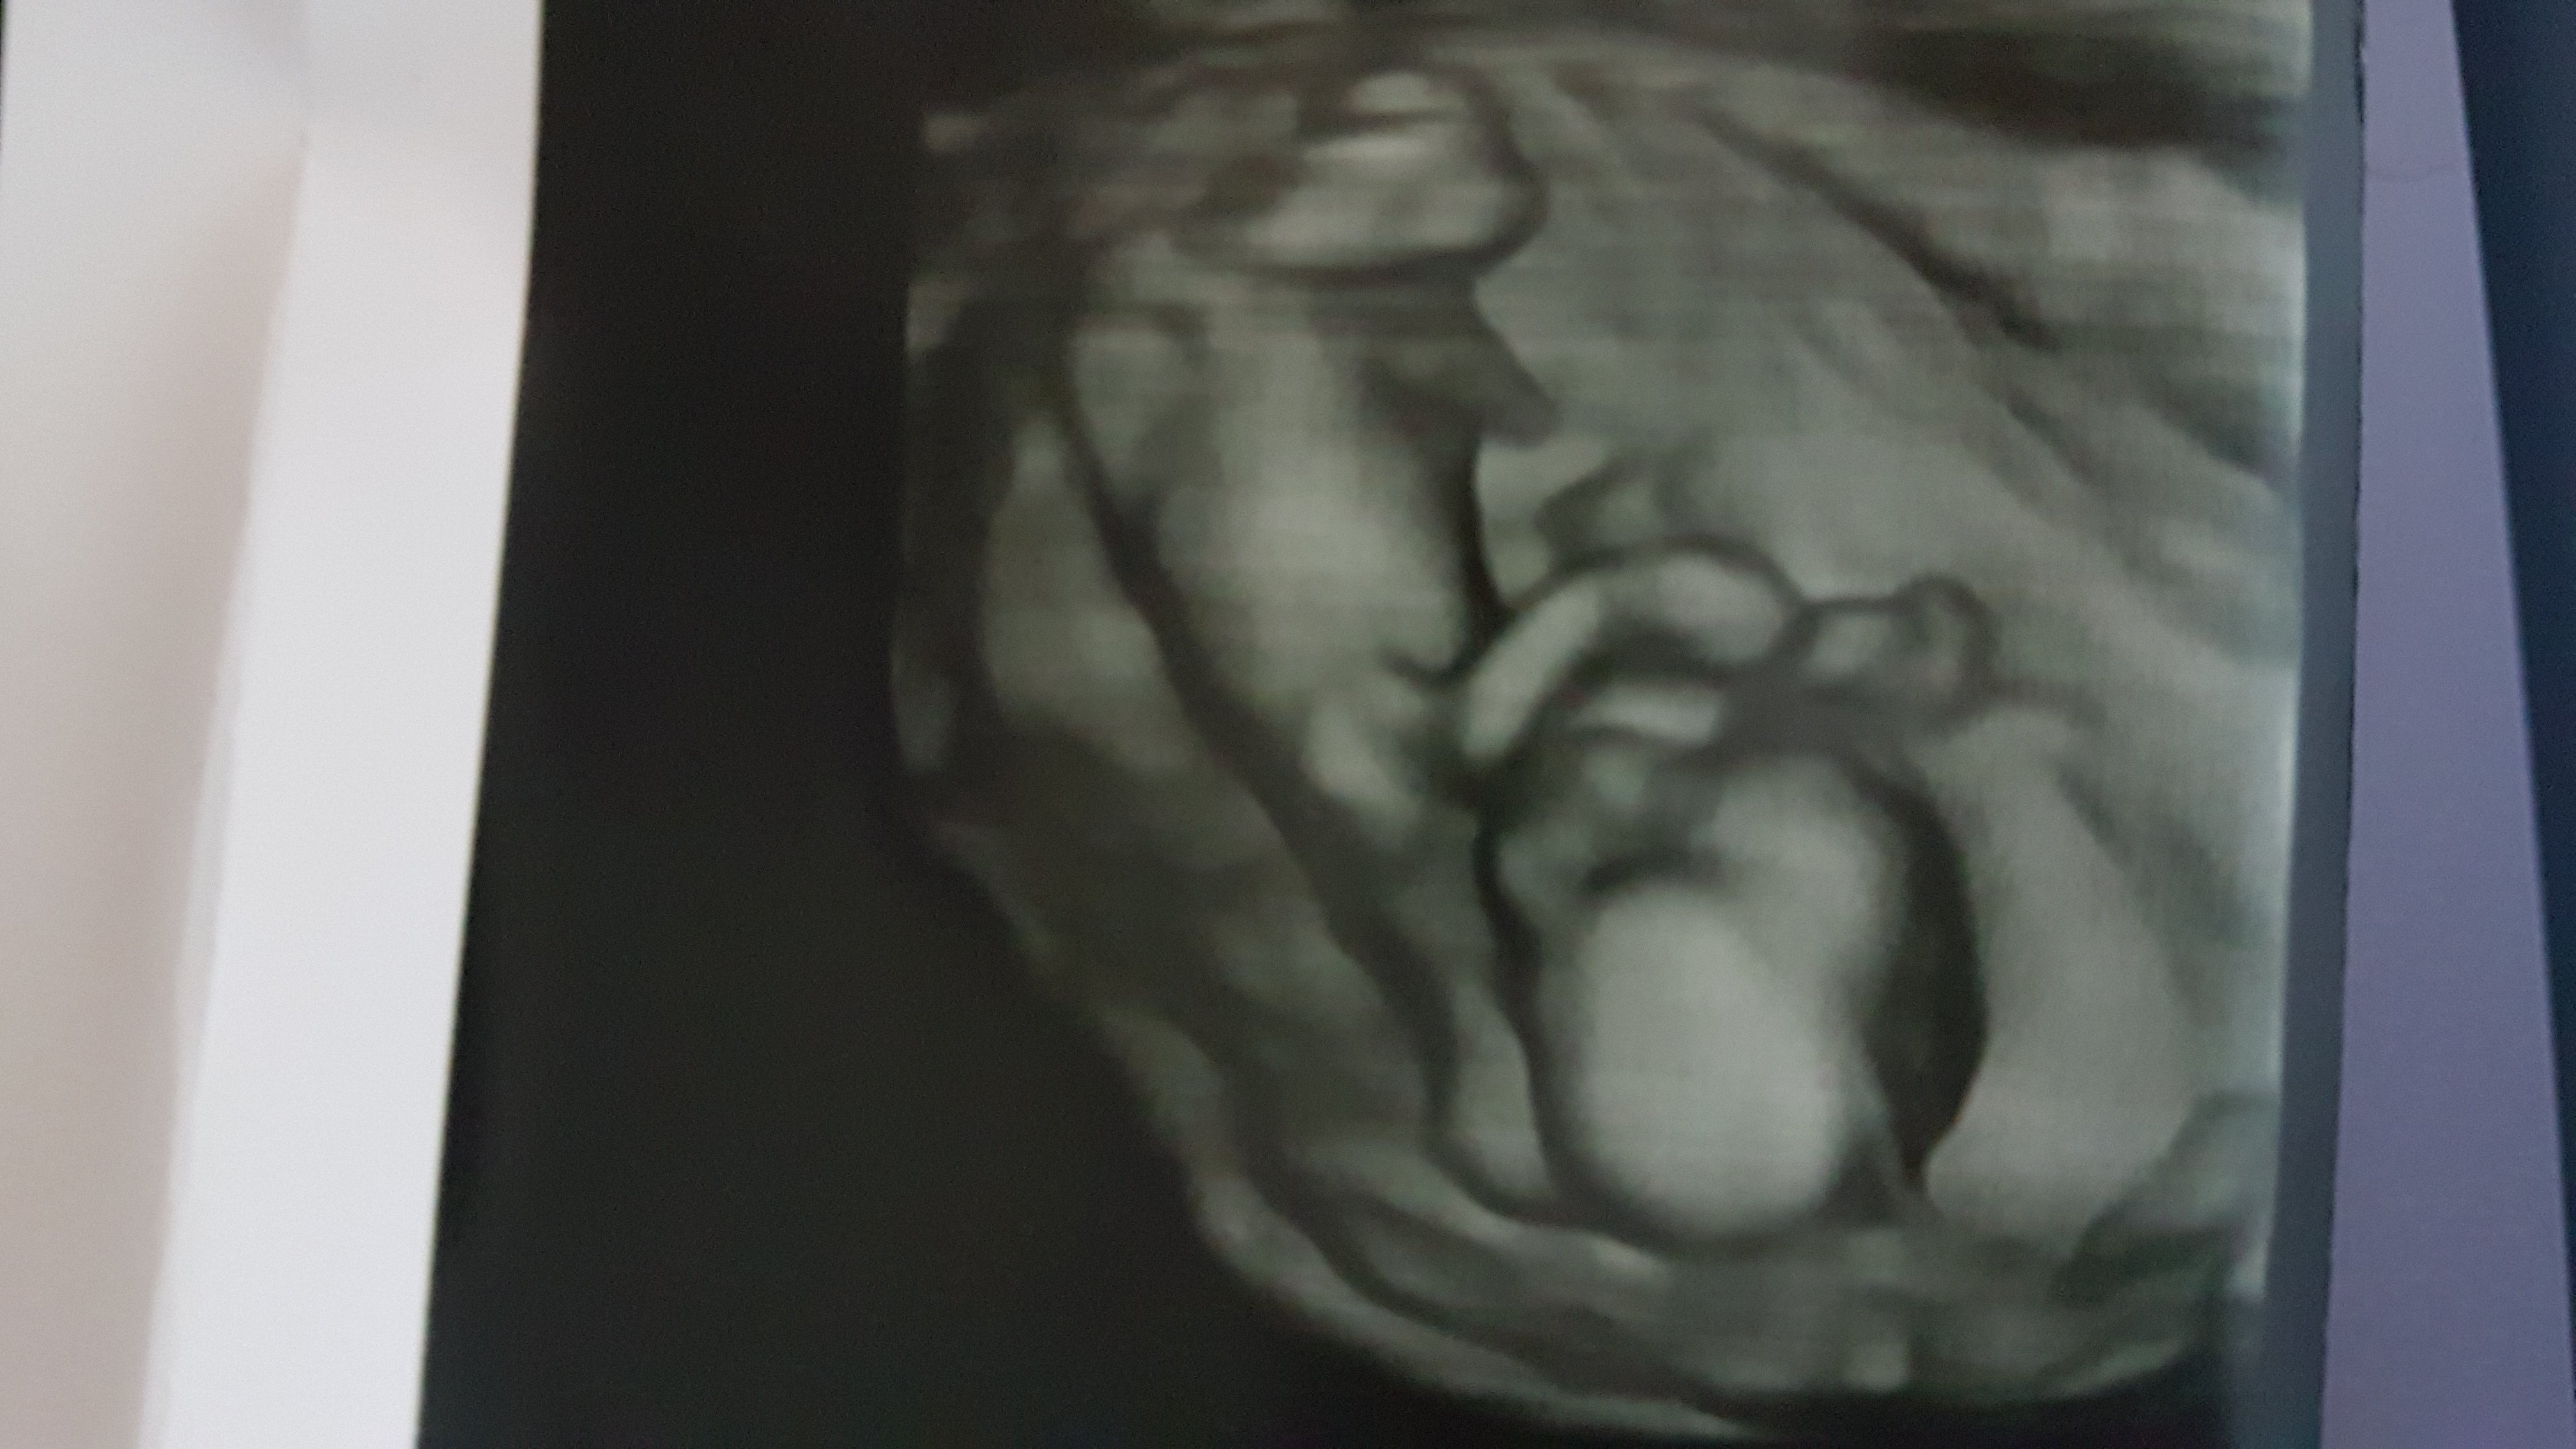

I jak zobaczylam niunie ktora ma juz ponad 8 cm to mi wszystko przeszlo

Przesylam zdjecie chyba Hani ❤ przepraszam nie chce niogo urazic zdjeciem ale nie mam sily przesylac napriv